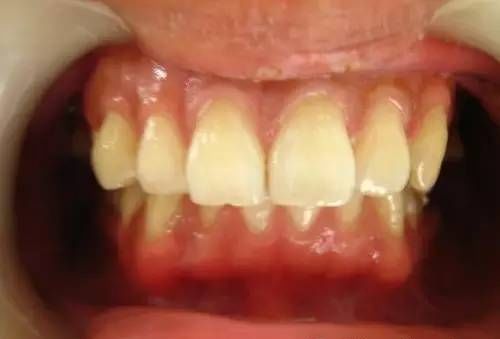

最近接诊了一些牙周炎的病人,颇有些感慨。牙周炎在中国的老百姓当中是比较普遍的。以往人们对于牙周的重视程度不够,结果导致后期牙根暴露、牙齿松动,甚至最后不得不拔掉松动的牙齿。